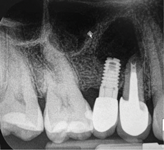

Report of a case. A 45-year-old male patient was referred with pain, redness, and swelling around an implant in the position of the maxillary right second premolar. The implant had been in clinical function for 3 years. The patient had a history of endodontic treatment and tooth loss and subsequent implant treatment in the region. Radiographic examination showed a radiolucency around the apical portion of the implant and the adjacent tooth. The implant was clinically stable and the neighboring tooth No. 4 was considered to have a periapical lesion. Initially, the patient received antibiotics (clindamycin 300 mg, three times daily) and was followed up for 2 weeks. After this, the patient was scheduled for surgical exploration of the implant area. Treatment comprised elevation of a full-thickness flap, curettage of the apical lesion, irrigation with saline, and removal of the apical portion of the implant and apicoectomy of the adjacent tooth (Figure 3 and Figure 4), including a guided bone regeneration (GBR) procedure with a cancellous particulate allograft and 20 mm x 30 mm pericardium membrane. Granulation tissue was sent for histopathology analysis, which revealed a periapical inflammatory infection. At the 4-month follow-up increased radiographic bone density could be observed consistent with the formation of bone not only around the implant apex but also along the root of tooth No. 5 (Figure 5).

Fig 3. Intraoperative radiograph demonstrating apical resection of implant and tooth.

Figure 3

Fig 5. Postoperative radiograph showing defect ossification after 4 months.

Figure 5